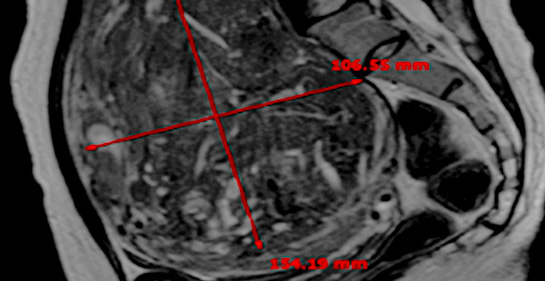

MRI촬영으로 자궁근종의 상태(위치, 개수, 크기, 모양 등), 자궁근종의 혈액공급 및 혈류,

자궁근종과 인접한 주요장기 및 구조, 초음파 발사경로의 확보 등을 분석함. 또한, 정밀초음파는 제거할 자궁근종의 개수, 자궁근종의 치료 슬라이스 수와

각 슬라이스의 체적, 근종제거마진, 근종과 인접한 장기와의 상관관계 등을 분석합니다.

시술 전 MRI검사 결과를 바탕으로 자궁근종이나

자궁선근증 등 종양의 위치, 크기, 모양 등 정확하게 파악